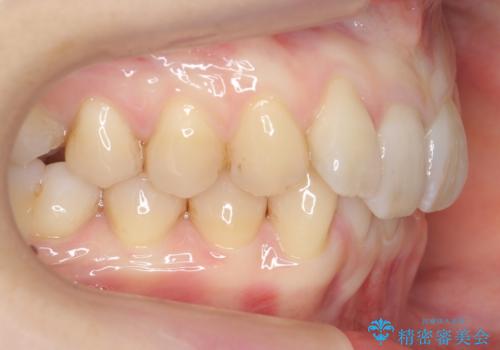

- 前歯のがたつきを主訴に来院。

下の前歯は生まれつき1本少ない状態でした。

左上の犬歯が入りきらずねじれており、かみ合わせもずれていました。

左上の小臼歯を1本抜いて治療しています。

前歯は内側に傾いており(ラビッティング)、過蓋咬合(深いかみ合わせ)を呈していました。

難しい治療でしたが綺麗に咬み合わせることができ、また前歯もしっかり当たるように治療できました。